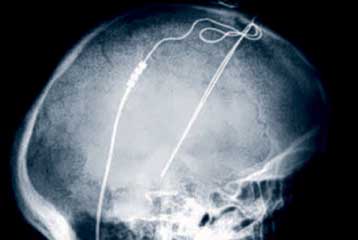

The device is implanted beneath the skull and sends electrical impulses deep within the brain.

The placement of the pacemaker occurred in the following by placing two fine wires and a pacemaker for each patient.

One end of a cable connected to the right side of the brain and is the second to the left. The wire was passed under the skin on the neck of patients reaching up high in the chest, where they were connected to the pacemaker.

This process is similar to that used for the placement of the cardiac pacemaker.